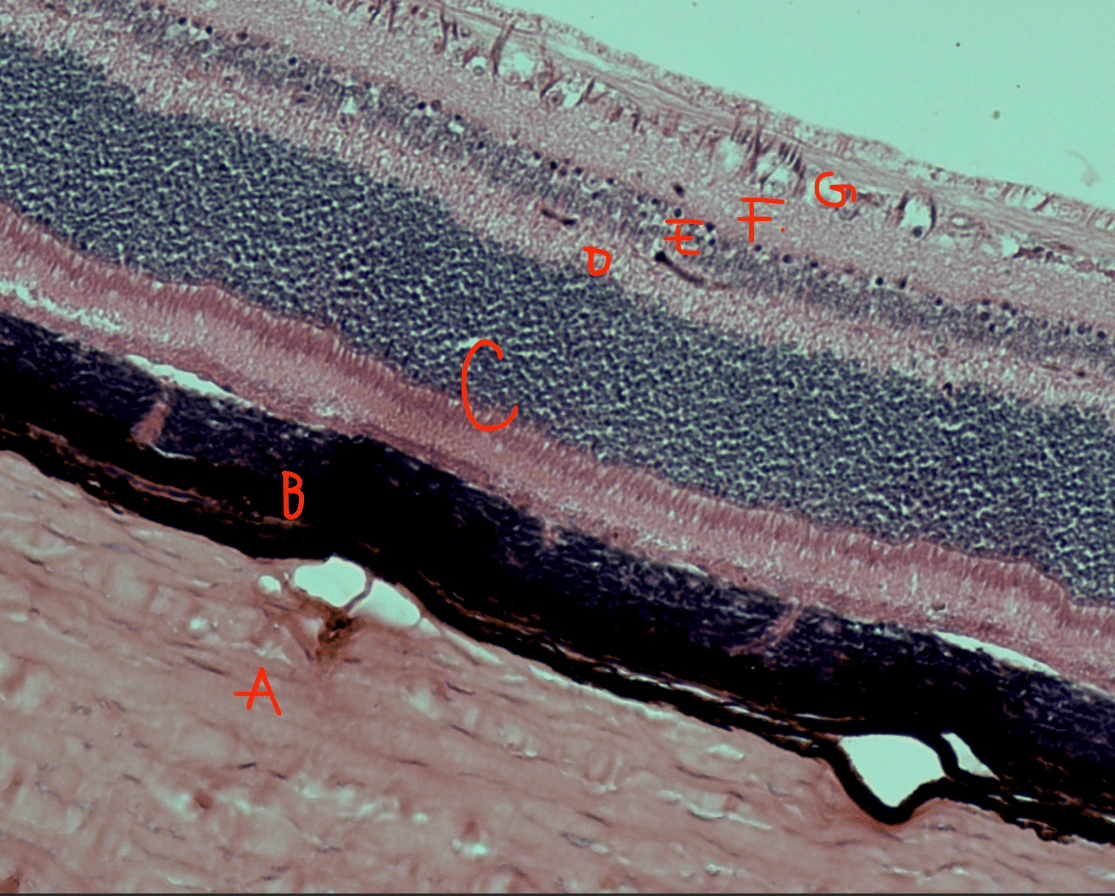

Label C, D, E, F, G

C: Photoreceptor layer

D: Outer synaptic layer

E: Bipolar cell layer

F: Inner synaptic layer

G: Ganglion cell layer